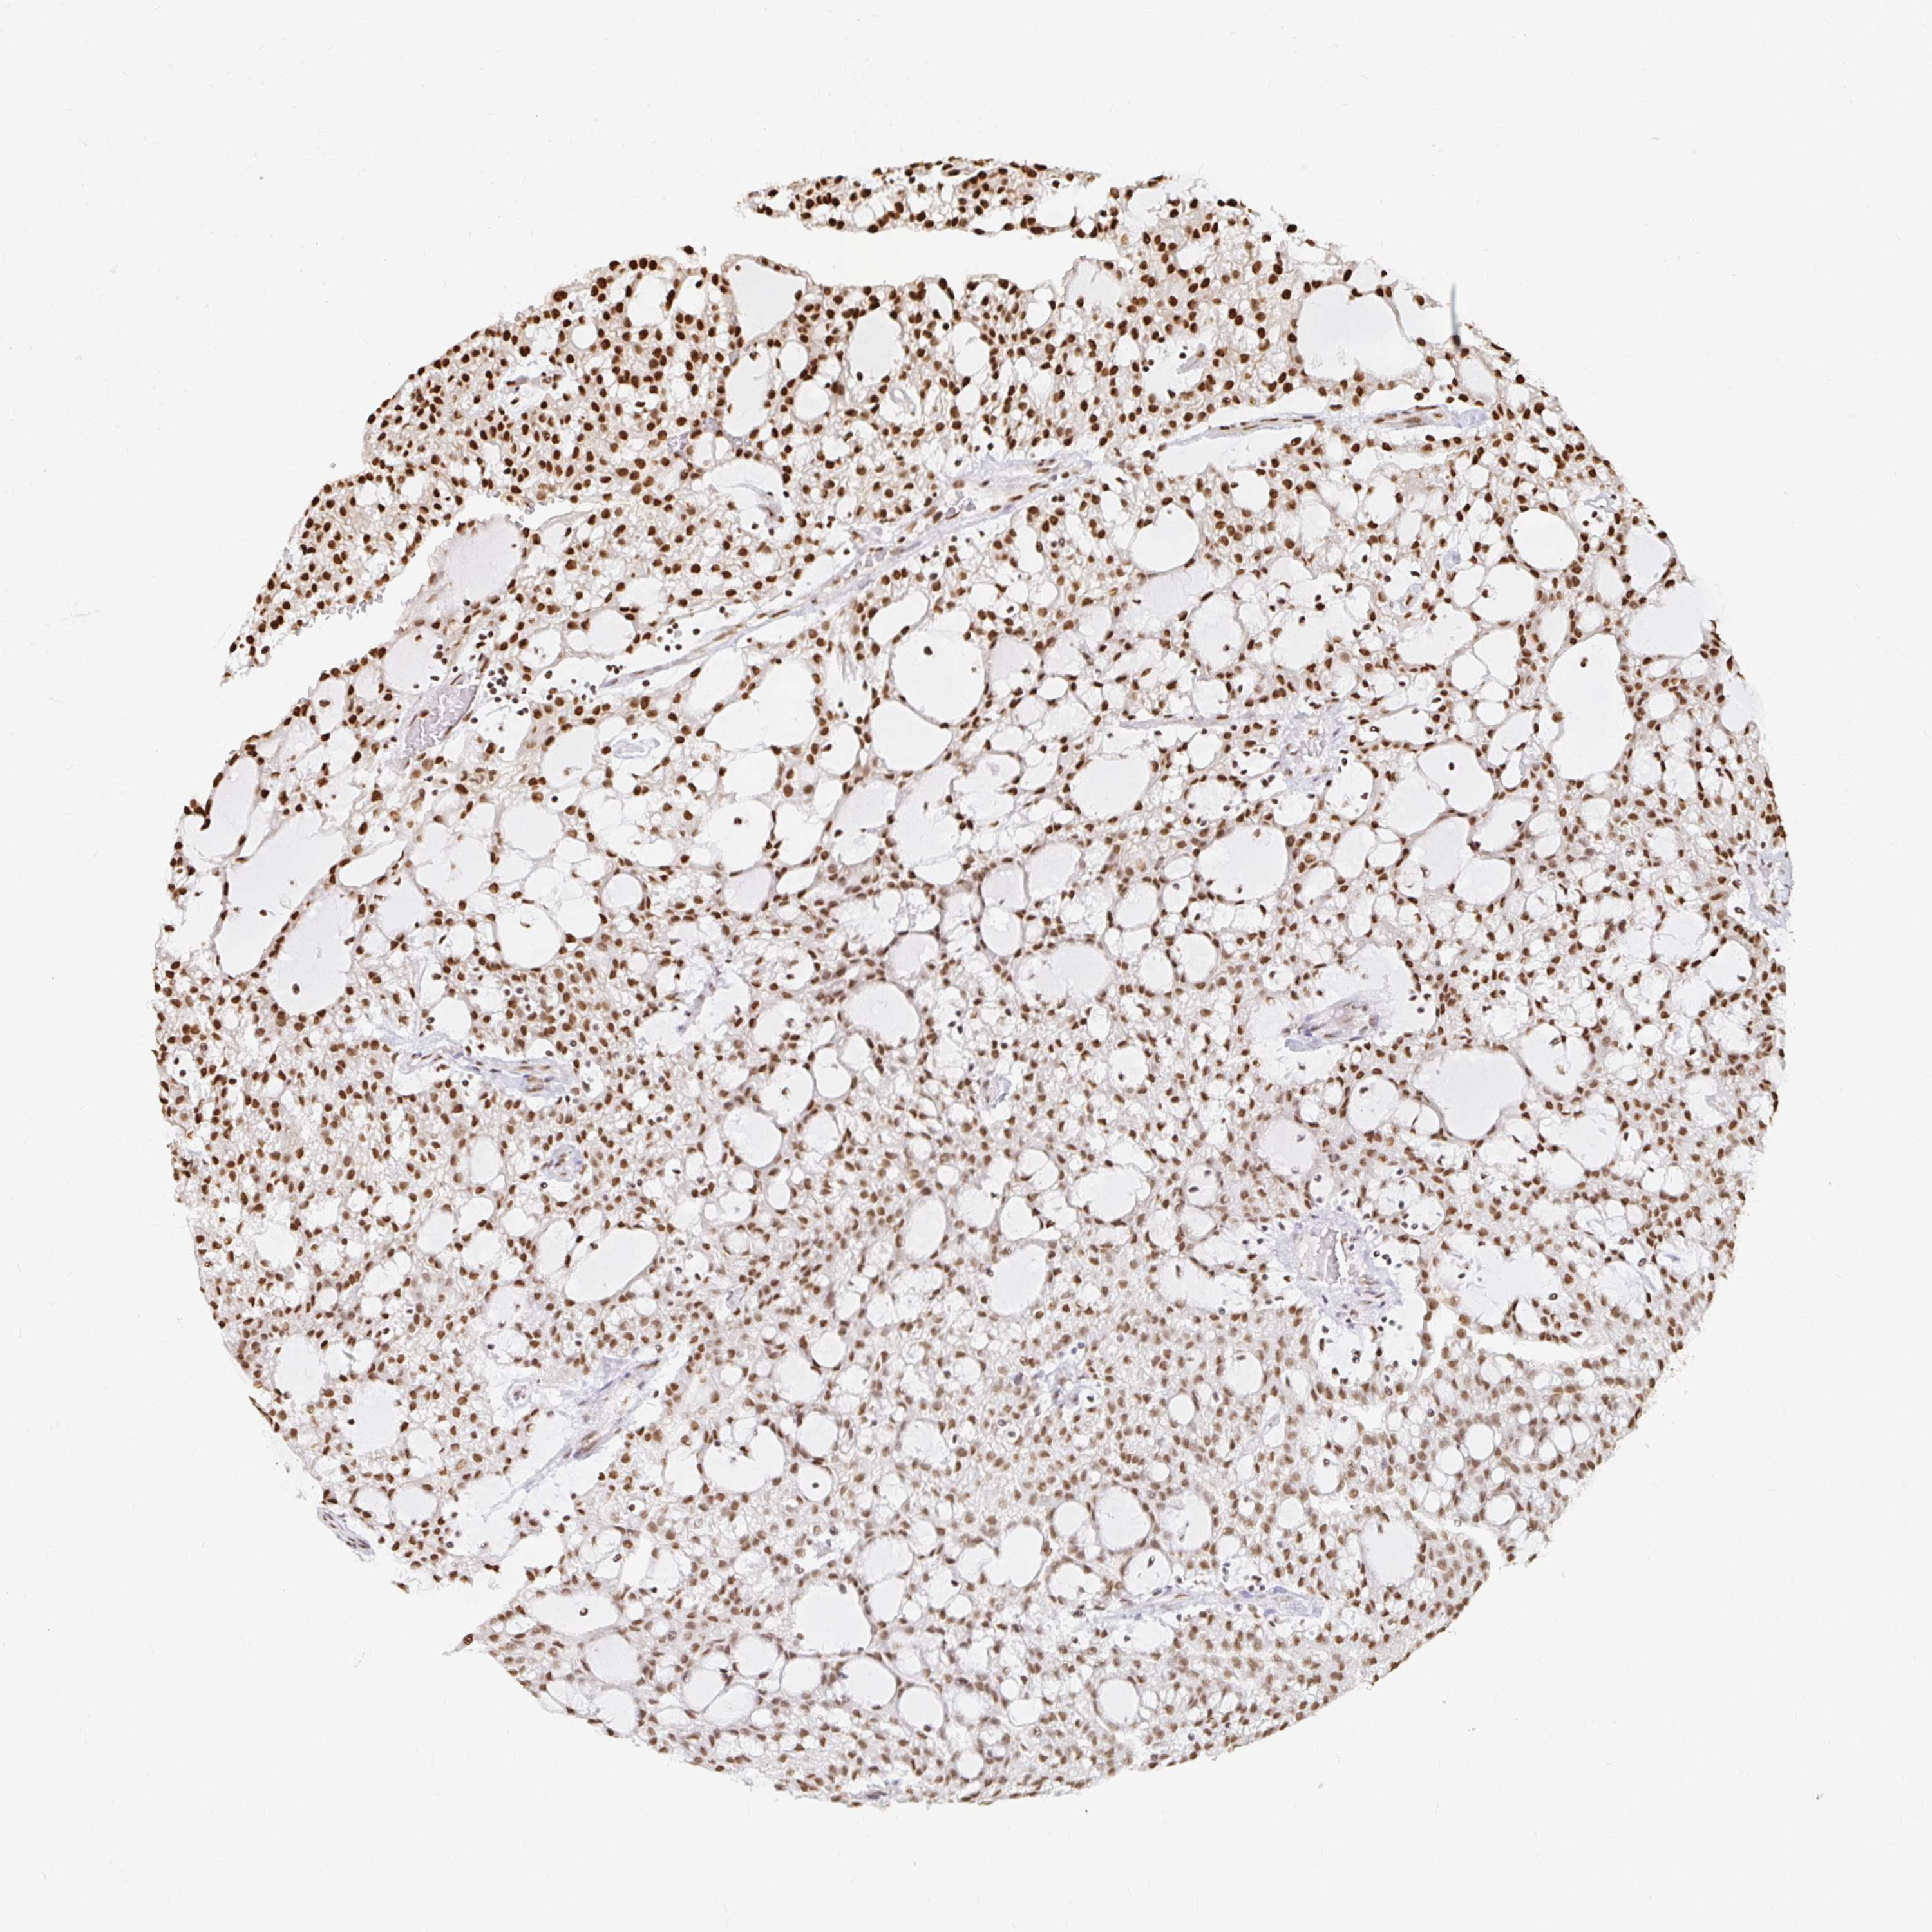

KIDNEY RENAL CLEAR CELL CARCINOMA (TCGA) - Interactive survival scatter ploti

The Survival Scatter plot shows the clinical status (i.e. dead or alive) for all individuals in the patient cohort, based on the same data that underlies the corresponding Kaplan-Meier plots. Patients that are alive at last time for follow-up are shown in blue and patients who have died during the study are shown in red.

The x-axis shows the expression levels (FPKM) of the investigated gene in the tumor tissue at the time of diagnosis. The y-axis shows the follow-up time after diagnosis (years). Both axes are complimented with kernel density curves demonstrating the data density over the axes. The top density plot shows the expression levels (FPKM) distribution among dead (red) and alive patients (blue). The right density plot shows the data density of the survived years of dead patients with high and low expression levels respectively, stratified using the cutoff indicated by the vertical dashed line through the Survival Scatter plot. This cutoff is automatically defined based on the FPKM cutoff that minimizes the p-score. The cutoff can be changed by dragging the vertical line or by entering a cutoff value in the square labeled "Current cut-off".

Under the Survival Scatter plot the p-score landscape (black curve; left axis) is shown together with dead median separation (red curve; right axis). Dead median separation is the difference in median mRNA expression between patients who have died with high and low expression, respectively. It is calculated as follows: median FPKM expression of dead patients with high expression - median FPKM expression of dead patients with low expression. This is intended to aid the user in visually exploring custom cutoffs and the associated p-scores and dead median separation.

Individual patient data is displayed and can be filtered by clicking on one or more of the category buttons on the top of the page. Categories describing expression level and patient information include: high, low, alive, dead, female, male and tumor stages. The scale of the x-axis can be toggled between linear and log-scale by clicking on the "x log" button. Mouse-over function shows TCGA ID, patient information and mRNA expression (FPKM) for each patient.

& Survival analysisi

Kaplan-Meier plots summarize results from analysis of correlation between mRNA expression level and patient survival. Patients were divided based on level of expression into one of the two groups "low" (under cut off) or "high" (over cut off). X-axis shows time for survival (years) and y-axis shows the probability of survival, where 1.0 corresponds to 100 percent.

HNRNPU is potential prognostic, high expression is favorable in Kidney Renal Clear Cell Carcinoma (TCGA)

: 166.47

Average pTPM 137.9

Number of samples 521